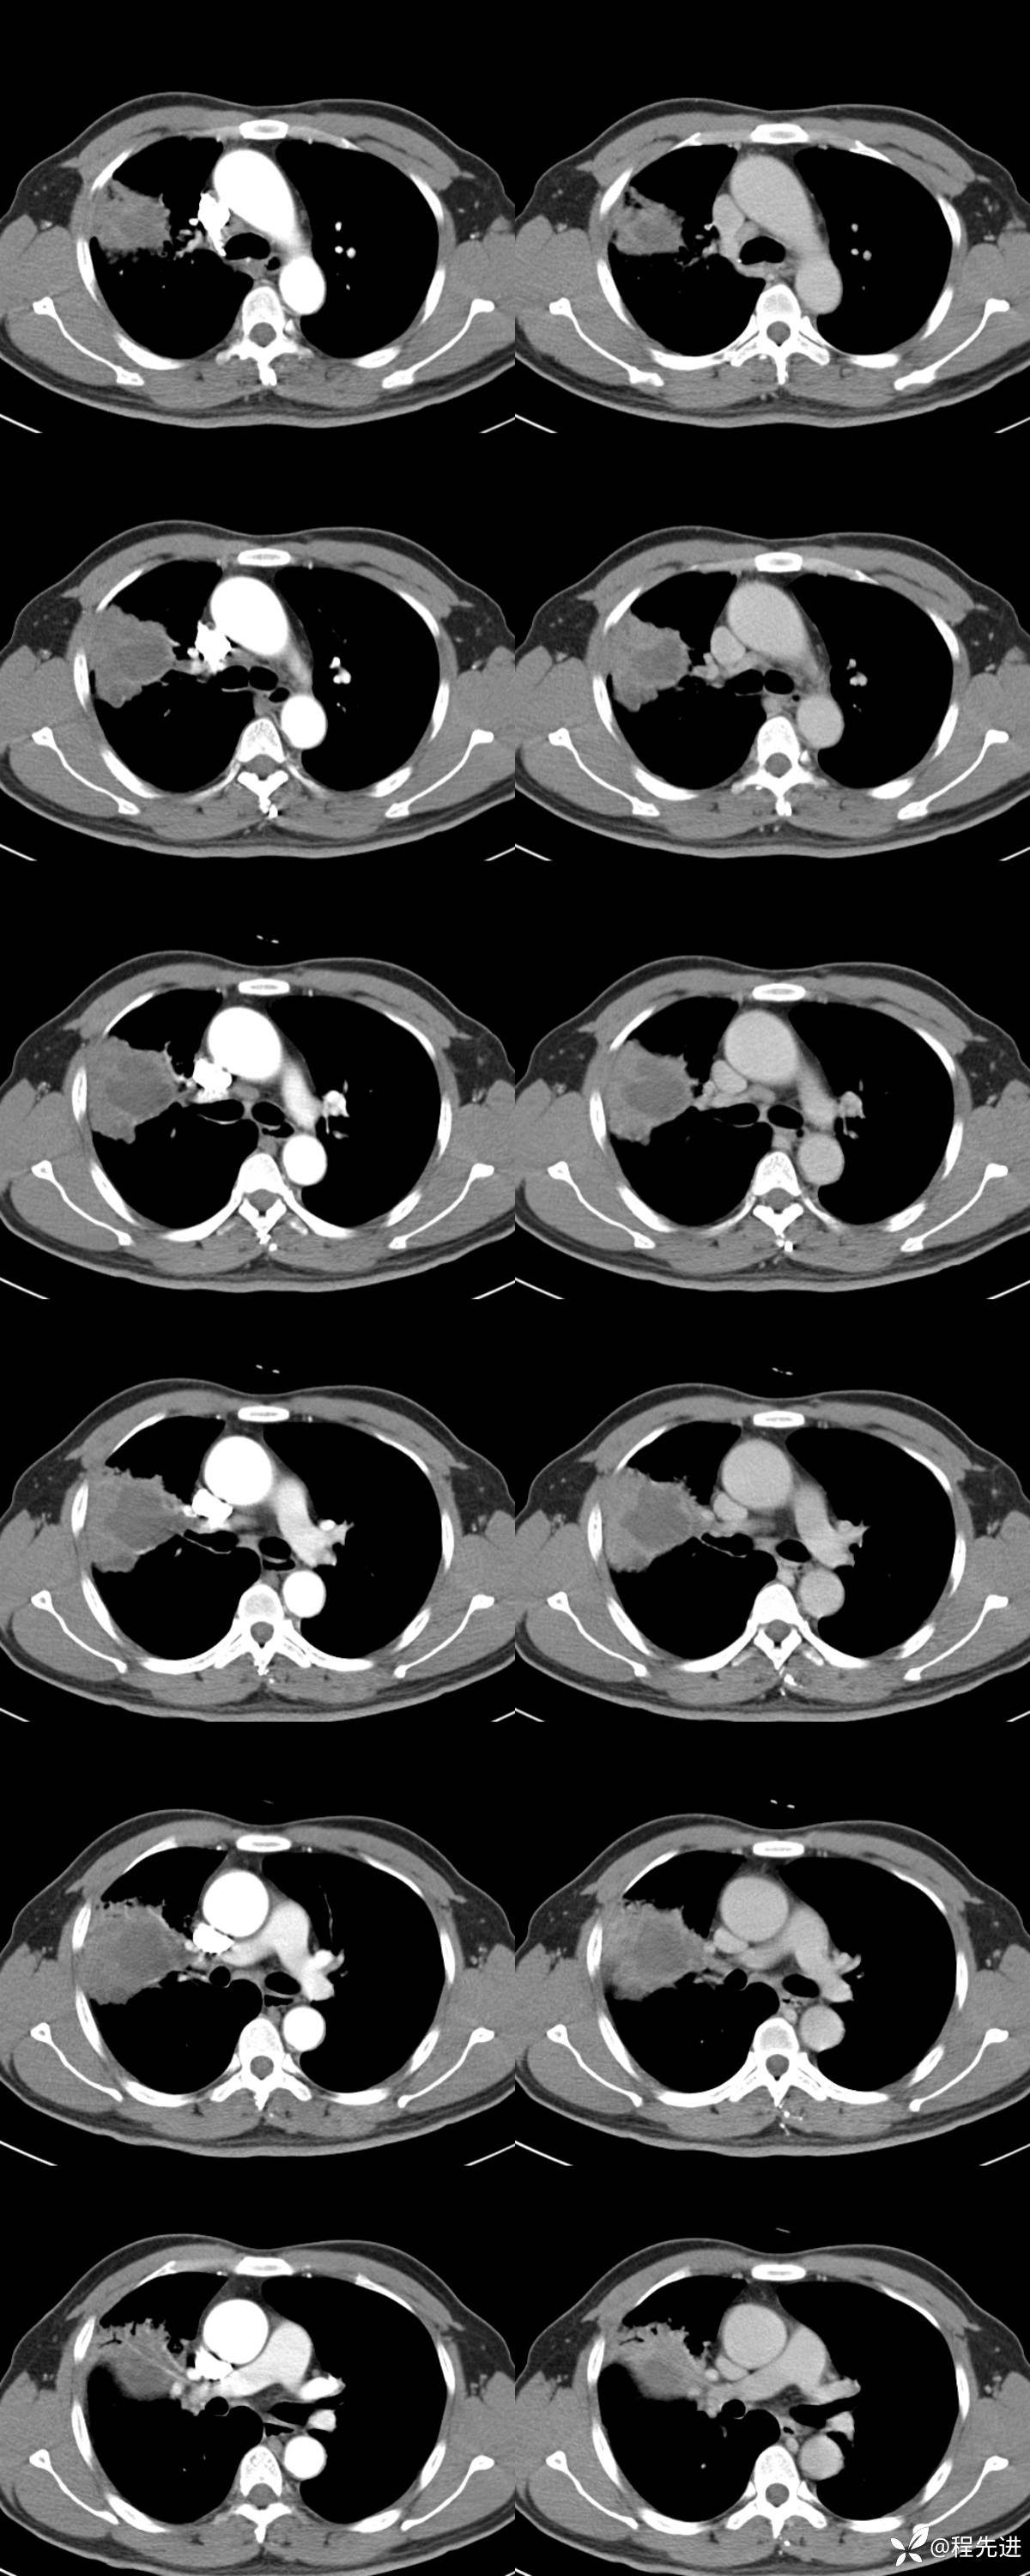

增强扫描:

左排动脉期,右排静脉期(图像连续):

CT值:

实质有强化区,平扫:40,动脉期:54,静脉期:71HU

中央低强化区,平扫:23,动脉期:28,静脉期:27HU